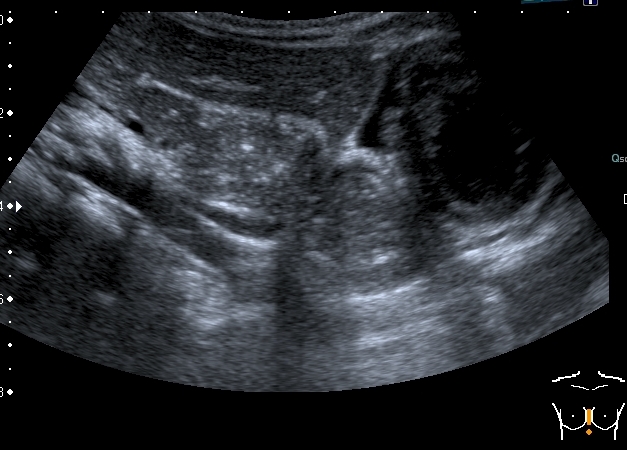

Девочка 4-х лет, жалобы на длительный кашель (оеоло 1-го месяца). В поликлинике выполнена рентгенография органов грудной клетки, выявлены изменения (какие - пока не скажу). Госпитализирована. Направлена на УЗИ сердца. При УЗИ - в самом сердце - патологии не выявлено, но позади него к правому предсердию прилежит полостное образование с акустически неоднородным содержимым.